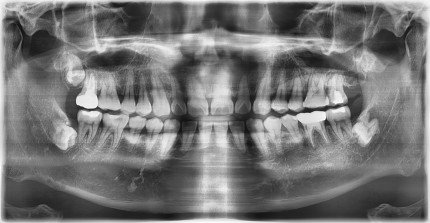

쿨쿨플란트치과 고난이도 사랑니발치 케이스

쿨쿨플란트치과 사랑니, 매복치발치 치료 전후사진